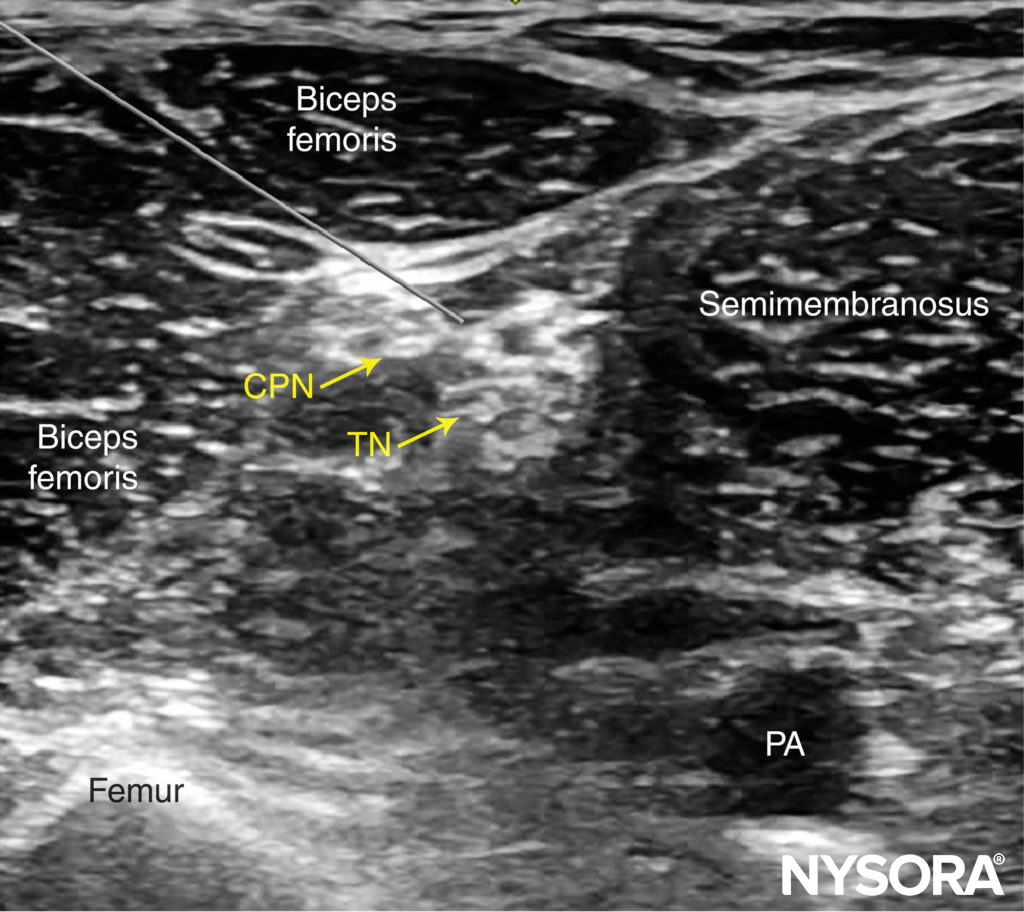

Poplietalblock

Der Poplietalblock dient der Blockade des N. ischiadicus in der Vloka-Scheide kurz vor seiner Aufteilung zum N. tibialis und N. fibularus (peroneus) communis. Somit kann beinahe der gesamte Unterschenkel und Fuß betäubt werden. Die mediale Seite des Unterschenkels gehört dem N. saphenus, einem Ast des N. femoralis. Will man also z.B. eine Verplattung des Unterschenkels oder Zehen- bzw. Unterschenkelamputation operieren, so bietet sich aus anästhesiologischer Sicht eine Blockade des N. ischiadicus sowie des N. saphenus an. Ich verabreiche zum N. ischiadicus entweder 20 ml Mepivacain 1,5% + 2 ml NaBic 8,4% + 1 ml Clonidin (0,15 mg) ODER 20 ml Ropivacain 0,5% + 1 ml Clonidin (0,15 mg). Den N. saphenus betäube ich separat mittels 5 ml Mepivacain 1,5% ODER 5 ml Ropivacain 0,5%. Dexamethason 4 mg i.v. gibt’s dann auch noch dazu. Sehr gerne lege ich bei chirurgischen Patienten mit ausgeprägten Wundstörungen am Unterschenkel / Fuß (z.B. aufgrund DM oder PAVK) einen Nervenkatheter zum Ischiadicus, was in einer potenten Analgesie auf der Station mündet (Infundieren von Ropivacain 0,2% mittels PCA – patient-controlled analgesie mit Schmerzpumpe). Ich erinnere mich gut an einen Diabetiker mit suizidalen Gedanken aufgrund höllischen Schmerzen in beiden Unterschenkeln bei ausgeprägtem diabetischem Fuß mit Wundheilungsstörung. Er war zu regelmäßigen Debridements gelistet. In der Regel analgosediere (Link) ich Patienten für den Block (und auch Kathetereinlage), weil die Lagerung ultraschmerzhaft ist. Dazu nutze ich regelhaft Esketamin. Ich blockierte beidseits Ischiadicus und Saphenus und legte dann beidseits Ischiadicusnervenkatheter ein. Fun Fact: dieser Patient hat in 45 Minuten fraktioniert 150 mg Esketamin verblasen und hat dabei stets spontan in Dissoziationsanästhesie geatmet! Die beidseitigen Schmerzkatheter waren auf Station eine extreme Erleichterung des Patienten; er konnte wieder lachen und mobilisiert werden und war extrem dankbar.